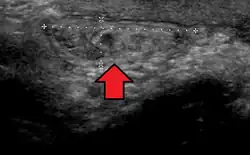

No diagnóstico de hérnias abdominais, a imagem é o principal meio de detectar hérnias diafragmáticas internas e outras hérnias não palpáveis ou não suspeitas. A tomografia computadorizada com múltiplos detectores (TCMD) pode mostrar com precisão o local anatômico do saco de hérnia, o conteúdo do saco e quaisquer complicações. A TCMD também oferece detalhes claros da parede abdominal, permitindo que as hérnias sejam identificadas com precisão.[9]